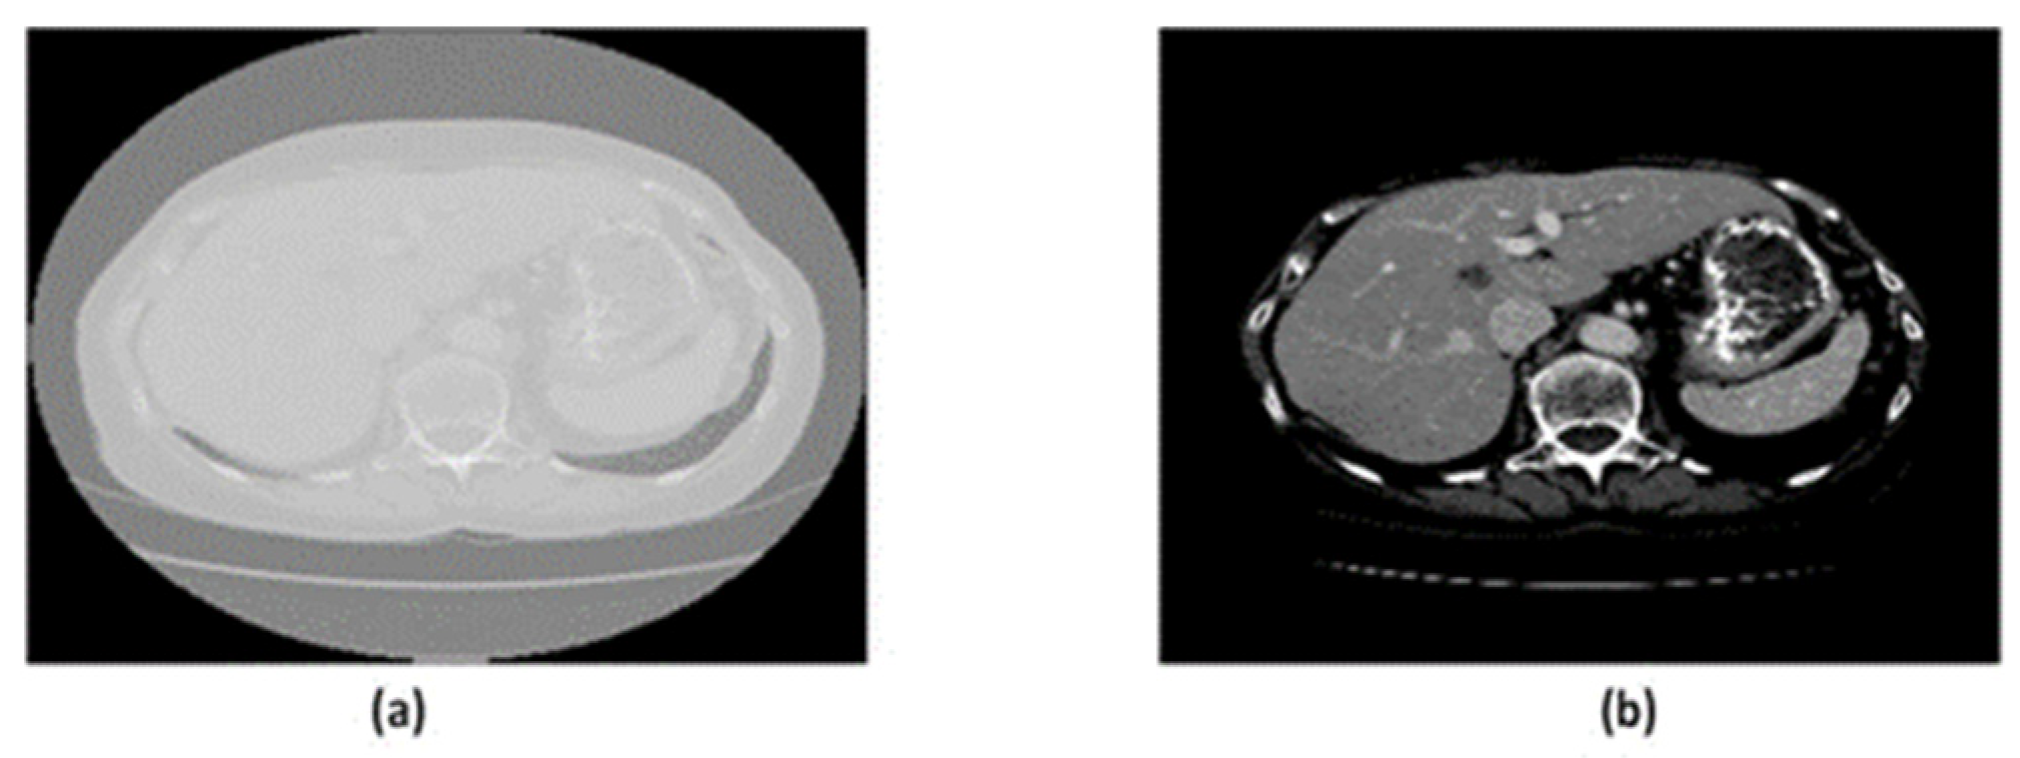

The intensity values for the NIfTI format range between −1000 and 2000, which is invisible to the human eye. Therefore, the intensity values are normalized using Hounsfield unit (HU) windowing in the range of [−100,400] for the liver. Also, a range of 0–255 is used for intensity value mapping. Sample images have been shown in Figure 2.

Figure 2. (a) Unprocessed Raw Image. (b) The image has been preprocessed using the Hounsfield unit.